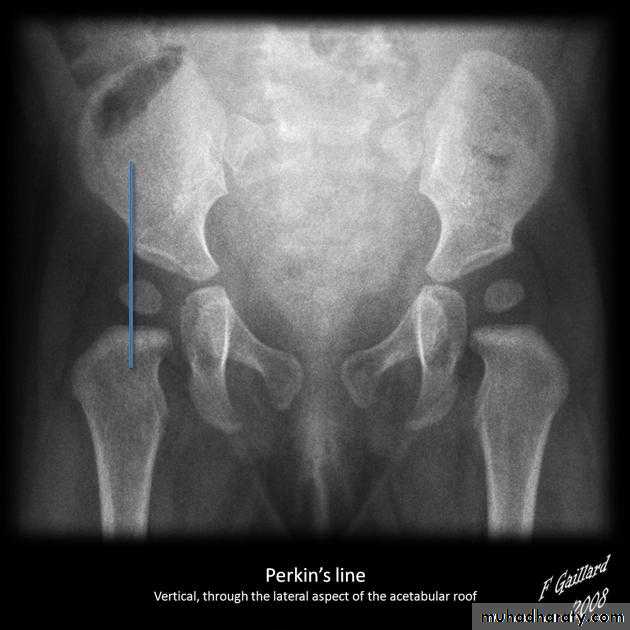

Shenton line is drawn along the inferior border of the superior pubic ramus and should continue laterally along the infero medial aspect of the proximal femur as a smooth line. If there is supero lateral migration of the proximal femur due to DDH then this line will be discontinuousPerkin line is drawn intersecting the lateral most aspect of the acetabuler roof & iliac creast

Q…By simple diagram draw pelvis with lines (shenton’s & Perkins line)